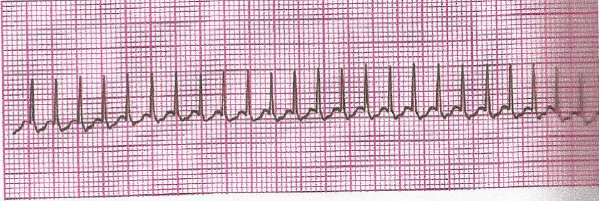

Lactente com miocardiopatia apresenta abruptamente irritabilidade, com período de sonolência, palidez cutânea, taquipneia com aumento do esforço respiratório, estertoração em bases pulmonares, FC = 260 bat/min, PAS = 60 mmHg, pulsos periféricos fracos e extremidades frias. É transferido para UTI com oxigênio e com dificuldade de acesso venoso disponível. Baseado na clínica e no ECG abaixo, assinale o diagnóstico dessa situação e a medida a ser adotada: